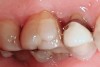

Figure 1   Classic presentation of the bruxism triad. Lateral wear pattern, generalized buccal tooth loss from erosion and abrasion, and history of sleep disruption.

Figure 1

Tooth wear is described in the literature as the loss of the constitution of the tooth and has been classified as being caused by attrition, abrasion, erosion, or a combination of these factors.9 As it relates to SB, tooth wear is reported to additionally cause tooth mobility, temperature hypersensitivity, and tooth fracture.10 While sleep bruxers and non-bruxers displayed significantly different amounts of wear over time, the contribution of tooth-on-tooth attrition to this wear is still controversial.11 It has been postulated that much of the wear could be erosion rather than attrition. Interestingly, those two factors are interwoven in the bruxism triad patient, magnifying the wear in this patient population (Figure 1).